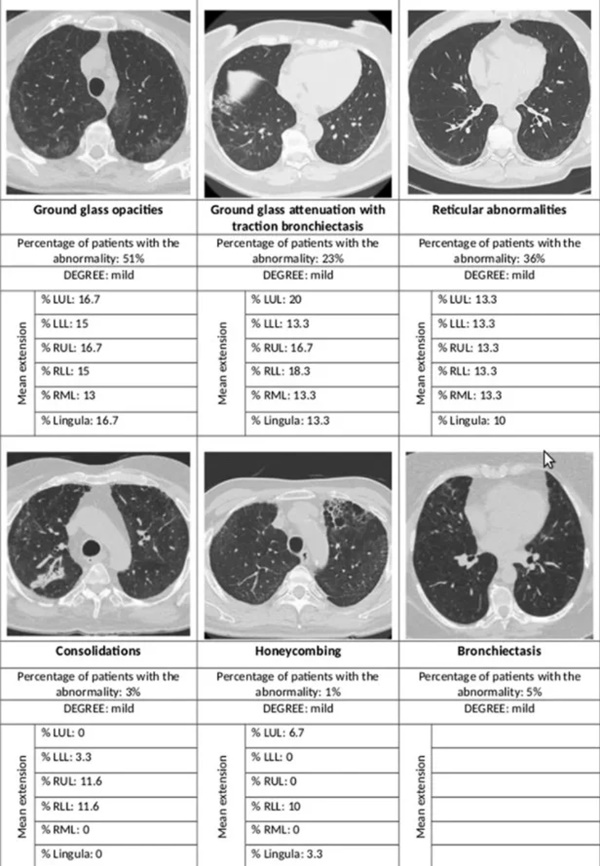

Hình chụp X-quang của bệnh nhân sau một năm khỏi Covid-19 xuất hiện các bất thường trên phổi. Ảnh: Respiratory Research.

Khi xem xét ảnh chụp CT phổi, nhóm tác giả phát hiện tổn thương ở nhu mô, tổ chức kẽ. Đặc biệt, hơn 50% bị tổn thương dạng kính mờ, 1/3 có bất thường dạng lưới, dưới 5% bị giảm tỷ trọng không khí trong các nang phổi mỗi bên. 44% bị tổn thương dạng kính mờ kèm theo giãn phế quản.

Trong số những người khuếch tán CO2 bình thường, gần 60% có những bất thường khi chụp CT. Tuy nhiên, khi khả năng khuếch tán CO2 bị suy giảm, tỷ lệ bất thường trên CT lên đến 77%. Con số này cũng tương tự với các tổn thương dạng kính mờ, tương ứng là 45% và 61%. Các bất thường dạng lưới lần lượt xảy ra ở 28% và gần 50% trường hợp.

Từ các kết quả này, nhóm chuyên gia kết luận phổi bị xơ hóa là tình trạng không phổ biến sau khi nhiễm nCoV. Chỉ 1% bệnh nhân có biến chứng này sau 12 tháng kể từ khi xuất viện.